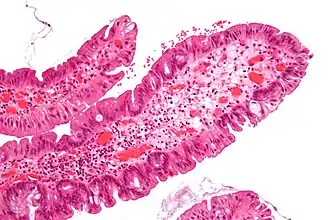

| Villous adenoma | 15%[16] to 40%[15] | Over 75% villous[14] |

| |

The villous subdivision is associated with the highest malignant potential because they generally have the largest surface area. (This is because the villi are projections into the lumen and hence have a bigger surface area.) However, villous adenomas are no more likely than tubular or tubulovillous adenomas to become cancerous if their sizes are all the same.[18]

- Villous adenoma: 40% risk of cancer

Micrograph of a villous adenoma. These polyps are considered to have a high risk of malignant transformation. H&E stain. -